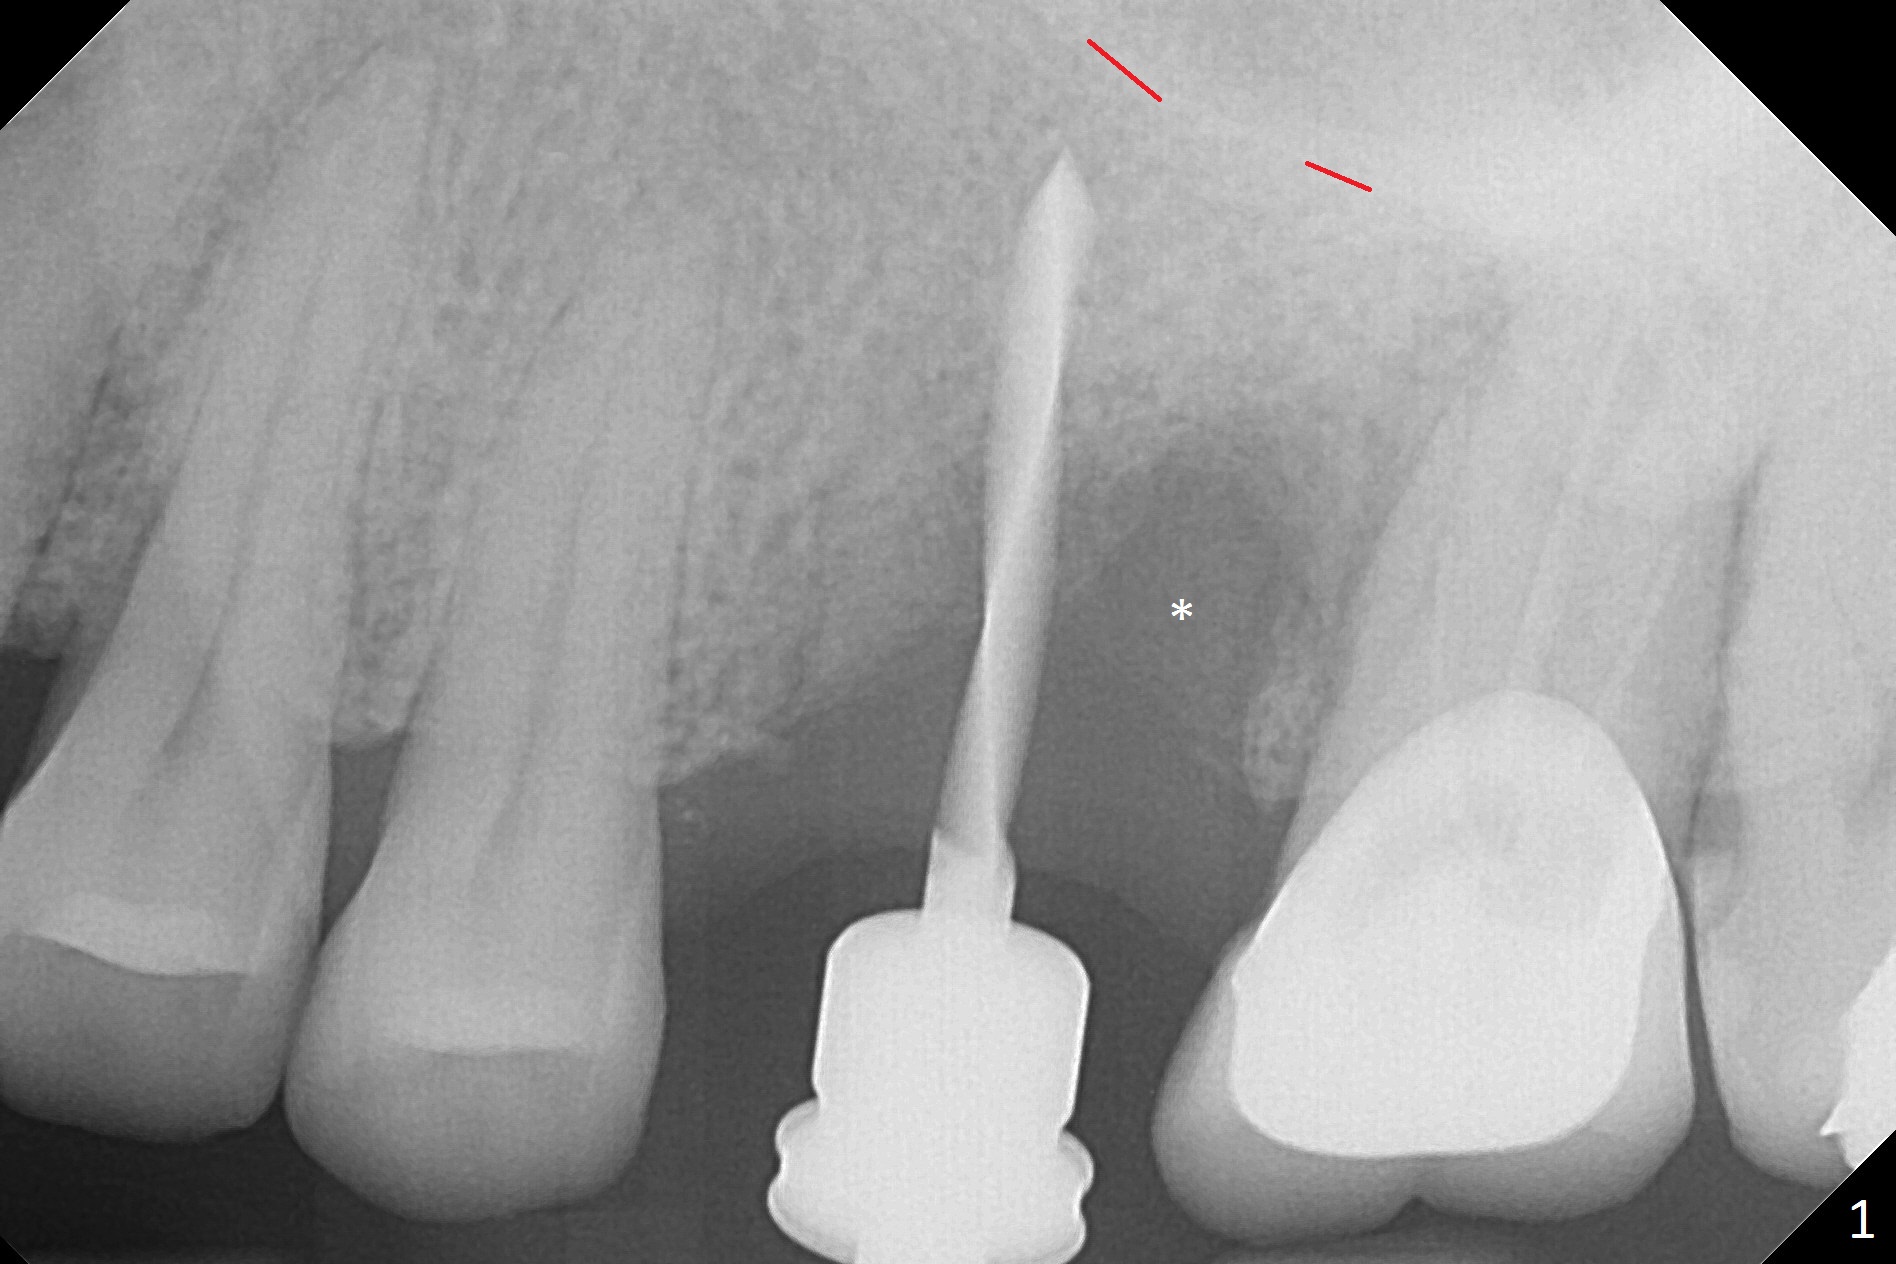

Magic Split is used to start access (flapless) and initial bone expansion at #14. The split does not go deep, since bone density is high in the deep portion. A 1.6 mm drill has to be used for 13 mm (Fig.1). Note the low bone density in the distobuccal socket (*). Later the osteotomy extends to 15 mm (gingival level). After 3.8 mm Magic Drill (MD) for 15 mm, a 4x11 mm dummy implant is placed with insertion torque of 60 Ncm (implant motor, Fig.2). After 4.3 mm MD, a 4.5x11 mm IBS implant is placed with insertion torque of 60 Ncm for implant motor >40 Ncm for torque wrench (Fig.3). The implant seems to be placed deep, but the buccal plate feels to be low. Following bone graft buccally, especially distobuccal (Fig.4,5 ^), a 5x4(3) mm abutment is placed. The buccal gingiva is torn during bone graft (Fig.6 >). Periodontal dressing is applied around the abutment (for increased retention) for wound protection.